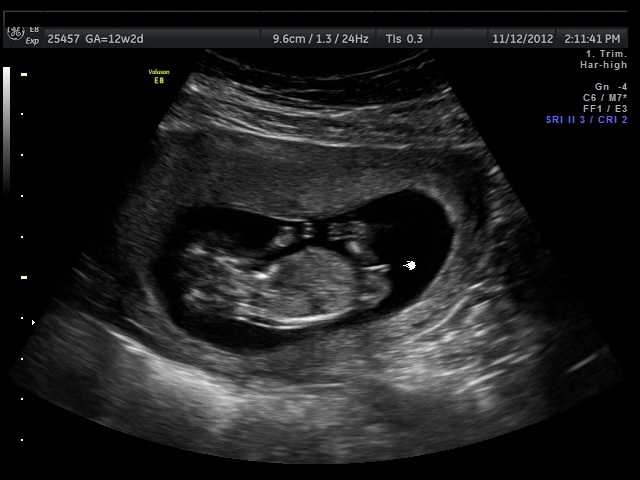

Hi, I just had my 12 week ultrasound yesterday and got a good "bottom shot". :o)

Any guesses?